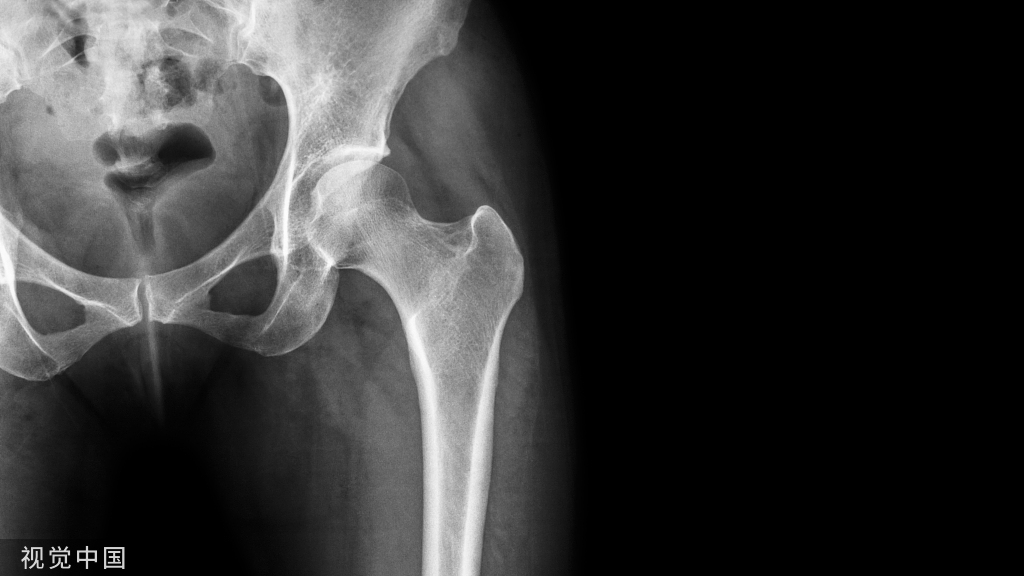

一般发病都是中老年,造成的原因是颈椎退化(骨刺、骨质疏松),造成脊柱变型、椎间孔狭窄压迫颈神经根所,若压迫第六条颈神经根,则会造成大拇指的麻木,若压迫第七条颈神经根,则会造成食指、中指、无名指之麻木,若压迫第八条颈神经根,则会造成小指的麻木,严重者亦会造成手部肌肉萎缩,无力握紧东西。颈椎退化更为严重的话,甚至有可能造成颈脊髓病变,此时不只手会麻,双下肢亦有可能麻木,僵硬无力,造成步行及大小便的的困难。患了颈椎病,做颈椎X光片可诊断,治疗措施有理疗、牵引和应用活血化淤的药物。平时,可常做一些缓慢活动颈部的保健操,并要注意睡眠时枕头高矮要适宜,一般以7-9厘米高为宜,不可过高或过低,软硬也要适中,睡姿要正确,可避免颈椎局部血管和神经组织受压而致手麻